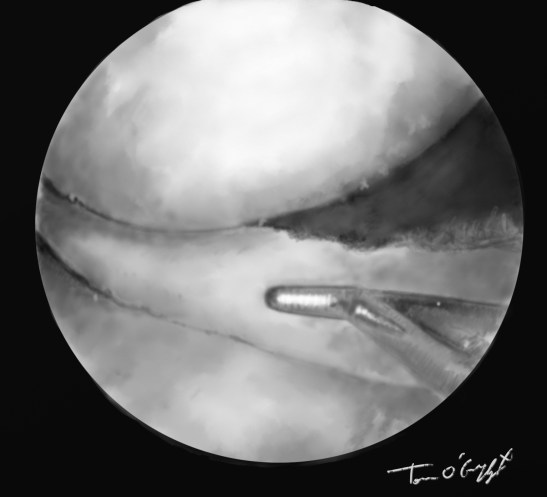

genou arthroscopie menisque crochet

arthroscopie luxation type anse de seau sur déchirure méniscale réduction au crochet

L’arthroscopie visualise alors exactement la déchirure méniscale, permet de réduire une luxation en anse de seau, de découper et régulariser une déchirure en languette, de suturer une fissure longitudinale ou en cas de désinsertion périphérique. En sachant que les atteintes externes ont une bonne chance de cicatrisation donc suture, et internes quasiment aucune donc exérèse.